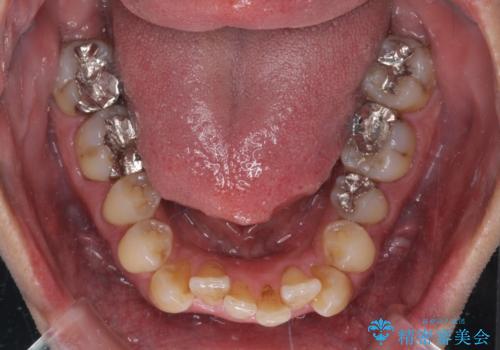

- 前歯のデコボコを気にして来院された患者様です。

下顎前歯のデコボコが特に強く、治療を早く終えることを考えるとワイヤー装置がお勧めですが、ワイヤー装置の異物感は避けたいのでインビザラインを希望されていました。

下顎にワイヤー装置を装着し、暫くしたところでやはりインビザラインにて矯正治療をしたいとのことで、インビザラインに切り替えました。

短い期間でしたがワイヤー装置を使用したことでデコボコが解消されたため、インビザラインの比較的短い期間で矯正治療を行うことができました。